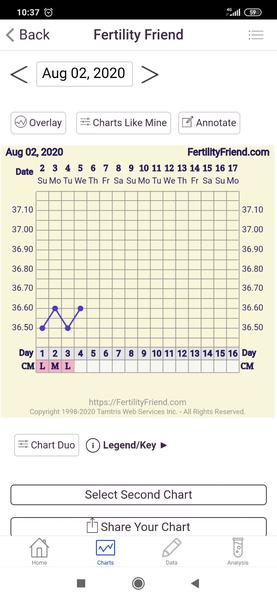

Ahojte. Prosím poradite mi ešte trošku? 2.8. som dostala ms, iba také malé splnenie, ďalší deň už to vyzeralo normálne, včera už slabšie a dnes už len spinim. Ide mi však o teplotu. Zaznacila som si 2.8. ako nový cyklus, avšak teplota mi vôbec neklesla pod ciaru. Dala som to aj dokopy bez zapisania ms, aby ste to lepšie videli na grafe. Myslite, že moze ísť o nejaký zápal, ale sa to je to normálne a predovulacna teplota môže byť v novom cykle kúsok vyššia? Cítim sa tak zľahka choro, trošku dutiny, únava a vyčerpanie.

@majka_3 naposledy 13 DPO a bol negatívny. Nemyslím si, že by išlo o tehotenstvo. Toho 3.8. bolo konečne normálne silne krvácanie. Teda nie úplne ako som mávala predtým, ale oproti posledným ms od potratu som teraz mala naozaj normálnu ms. Skôr sa bojim či nejde o nejaký zápal, infekciu, či nejakú poruchu..